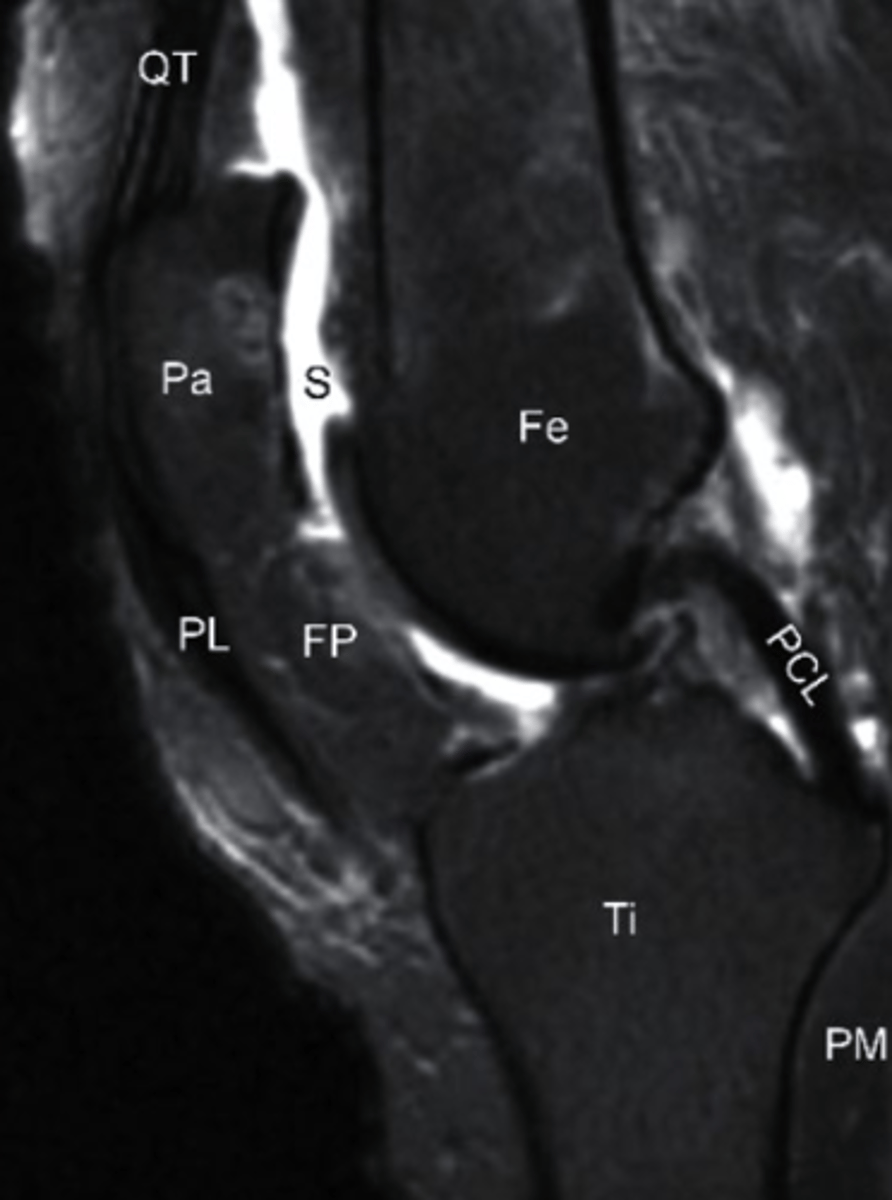

T2 MRI

what type of image is this?

a. T2 MRI

b. CT Scan

c. T1 MRI

d. conventional radiograph

bone bruise, T2 MRI

what can be seen on the medial tibial plateau in this image and what type of image is this?

a. tumor, T1 MRI

b. complex fracture, CT scan

c. bone bruise, T2 MRI

d. AVN, conventional radiograph